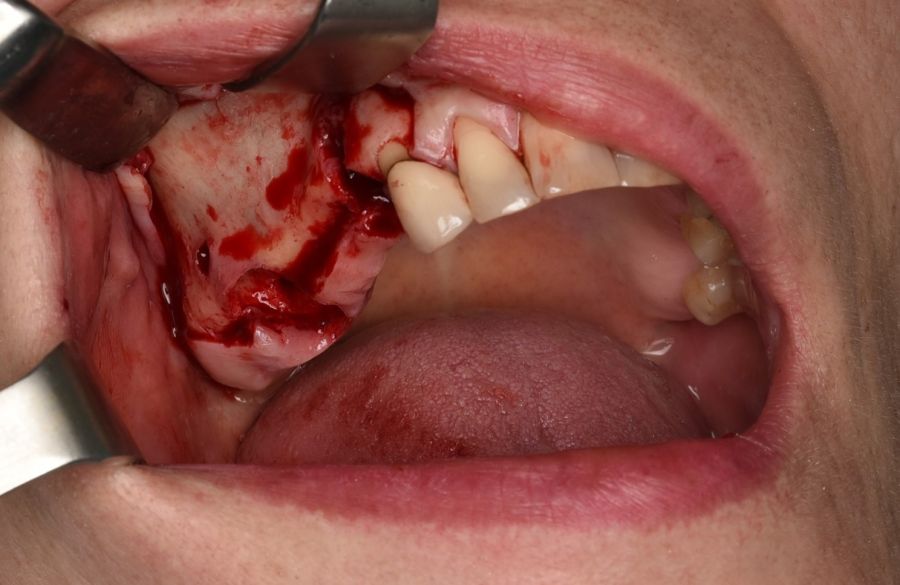

La intervención se llevó a cabo bajo anestesia local mediante técnica infiltrativa con Articaina/Epinefrina 40 mg/ml + 10 microgramos/ml solución inyectable (Inibsa®, Lliçà del Vall, Barcelona, España), de los nervios alveolares superiores derechos posterior y medio, nervio infraorbitario derecho con la técnica intraoral y nervio palatino anterior a nivel del agujero palatino posterior. Se realizó la sección de la prótesis distal a la corona 1.3 con turbina y fresa de Lindemann, y se procedió a la exodoncia de los pilares de la prótesis 1.4 y 1.7, y el legrado minucioso de sus lechos alveolares y del granuloma apical de 1.4.

El abordaje quirúrgico del seno se realizó mediante un colgajo a espesor total trapezoidal con una incisión supracretal con descargas verticales vestibulares mesial a 1.3 y distal a 1.7 (Figura 5).